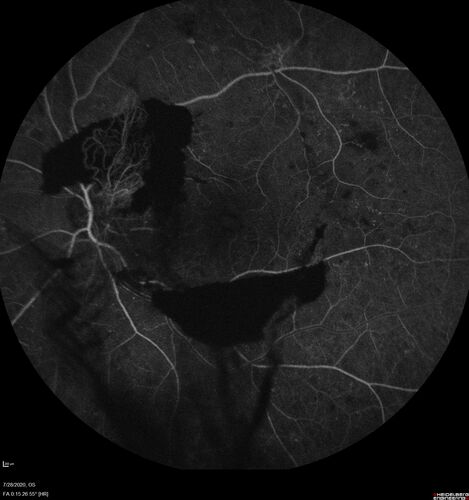

Proliferative Diabetic Retinopathy and vitreous hemorrhage left eye

44 year old man with type II diabetes for 14 years and no eye examinations in the last 5 years.  VA 20/40 right eye and 20/60 left eye.  Vision loss has been for about a week in the left eye.